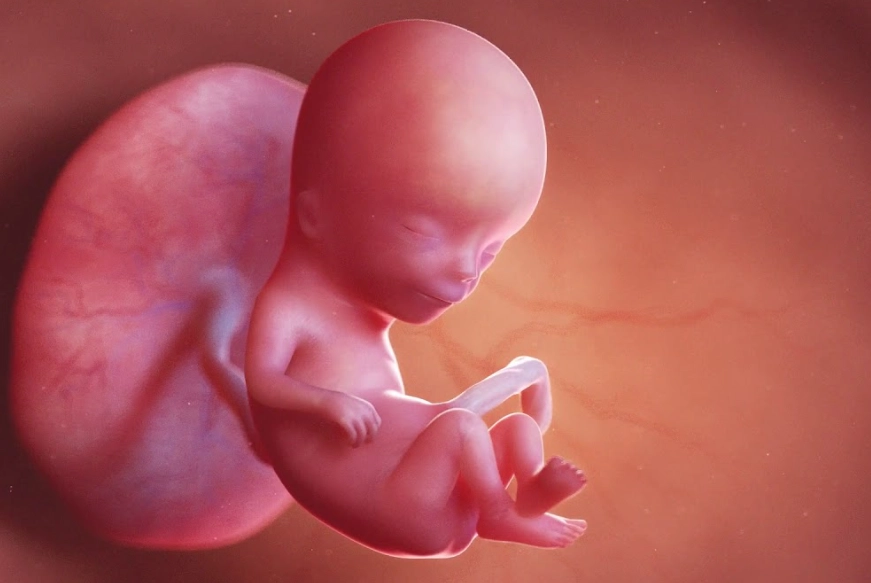

To understand the outside, you gotta know the inside. At 12 weeks, your baby has graduated from embryo to fetus—a huge milestone. They're about the size of a lime, roughly 2 inches long. But here's the key thing: your uterus. It's been growing, but it's only just now starting to rise up out of your pelvic cavity.

For most of the first trimester, your uterus is a pelvic organ. It's tucked neatly behind your pubic bone. By 12 weeks, it's about the size of a large grapefruit, and the top of it (the fundus) is beginning to peek above the pelvic brim. This is the very beginning of your "bump." But it's still low.